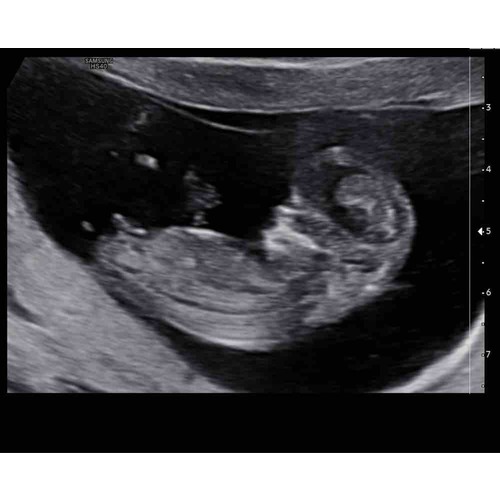

Foto 1: 13+1 week